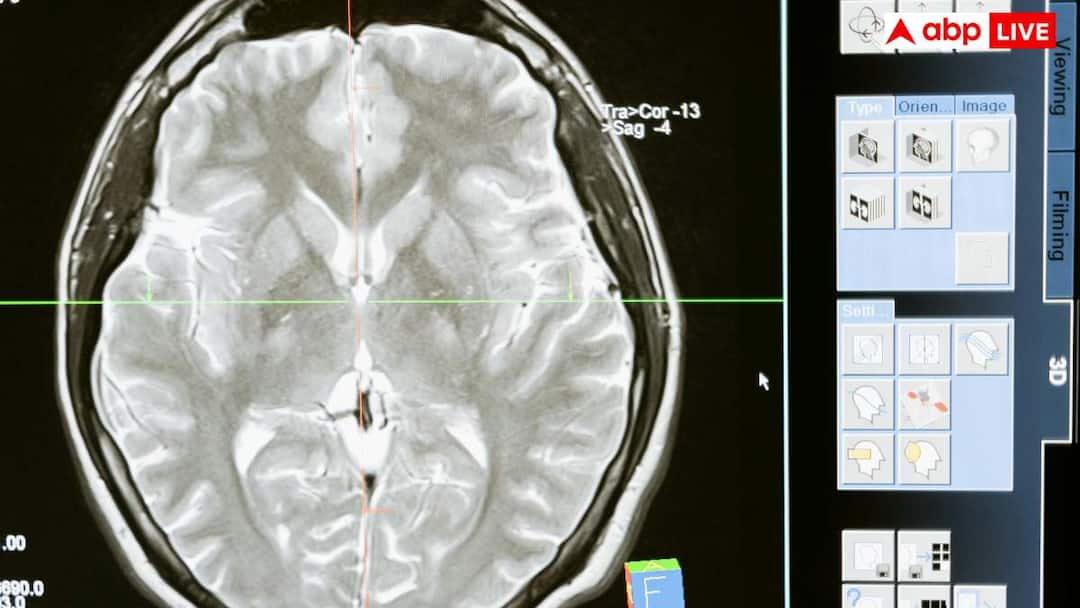

न्यूरोलॉजिस्ट की मानें, तो जब बच्चों में दौरे पड़ने के कारणों की जांच की गई और उनके दिमाग का स्कैन किया गया, तो दौरे पड़ने की मुख्य वजह पैरासाइटिक इंफेक्शन या दिमाग में मौजूद कीड़े पाए गए. इसके बारे में जानना हर किसी के लिए जरूरी है कि कैसे पैरासाइटिक इंफेक्शन बच्चों में दौरे पड़ने का मुख्य कारण बन रहा है.

दिमाग में पैरासाइटिक इंफेक्शन की मुख्य वजह न्यूरोसिस्टिकोसिस नाम की स्थिति है. यह एक ऐसी स्थिति है, जिसमें हमारे दिमाग में सूअर के फीताकृमि, जिन्हें हम पोर्क टैपवार्म भी कहते हैं, उनके अंडों के कारण यह समस्या होती है. ये अंडे कहीं भी हो सकते हैं, जैसे मिट्टी में, गंदे खाने में या किसी पत्तेदार सब्जियों के बीच में. इनके सेवन से ये अंडे हमारे खून के माध्यम से सीधे दिमाग में चले जाते हैं और वहां जम जाते हैं. ध्यान देने वाली बात यह है कि ये कीड़े नहीं होते, बल्कि उनके अंडे होते हैं.

न्यूरोसिस्टिकोसिस में दौरे पड़ने का सबसे बड़ा कारण यह है कि दिमाग इन अंडों से बचने के लिए कई तरह की प्रतिक्रिया करता है. जब ये अंडे दिमाग में पहुंच जाते हैं, तो हमारा शरीर उनके चारों तरफ सूजन पैदा कर देता है, ताकि बाहरी खतरों को एक जगह रोका जा सके. इसी सूजन की वजह से हमारे दिमाग की कोशिकाओं के बिजली के सिग्नल यानी इलेक्ट्रिकल सिग्नल में गड़बड़ी पैदा हो जाती है, जो दौरे पड़ने का कारण बनती है. जैसे-जैसे यह अंडा दिमाग में सड़ना शुरू करता है, वैसे-वैसे कई तरह की दिक्कतें होने लगती हैं, जिनमें सिरदर्द और दौरे पड़ना शामिल है.